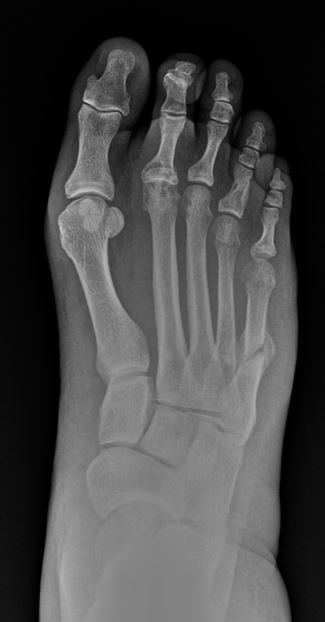

I haven't had radio yet but is that a lisfranc with 5th met transverse fx?

Weird case. 50ish year old male. I actually found this looking back through x-rays the other day. The guy had seen another DPM or ortho less than a year before for problems with the 5th metatarsal. He always had lingering issues even after it "calmed" down. Walked in acutely tender/painful/swollen with no protection or anything like that. Active smoker. History of a DVT. Scheduled for a major gastrointestinal surgery that he was literally flying to the other side of the country for. We came in and discussed a variety of options which I won't write to leave it open to discussion. Anyway. Sadly, he died a few months after the other surgery.

Questions you could ask yourself about the fracture - what are fracture findings of healing? What are clinical findings of healing? Does this fracture look - irregular? When is a fracture a non-union? What issues are raised by recurrent fractures of the lateral foot?

How about that 2nd MPJ?

Lol, I'm a first year so here goes nothing. The 2nd MPJ looks dislocated with possible hammer toe on it too? Either that the 2nd MPJ looks severely arthritic to me...

-On the AP view you can't see the joint space of the 2nd MPJ. DJD can cause joint space narrowing but so can a toe dorsally subluxating. There's also some degree of irregularity to the density of the joint/toe.